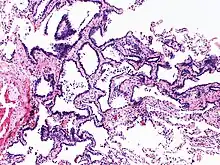

Image histologique de l'hyperplasie adénomateuse atypique.

L'hyperplasie adénomateuse atypique (HAA) est une lésion hyperplasique des pneumocytes bordant les alvéoles pulmonaires et présentant des anomalies cytonucléaires discrètes[1]. Ce terme est préconisé par l'Organisation mondiale de la santé dans sa classification des tumeurs de 2011, puis maintenu et précisé dans les versions de 2015 et 2021. Il caractérise une lésion glandulaire précurseur (précédemment dite lésion préinvasive) de très petite taille[2],[3].

Cette anomalie, de petite taille, inférieure ou égale à 5 mm[3], est une dysplasie, précancéreuse, précurseur de l'adénocarcinome pulmonaire in situ[4]. Le terme de carcinome bronchioloalvéolaire, autrefois employé pour décrire cette lésion est désormais abandonné[4].